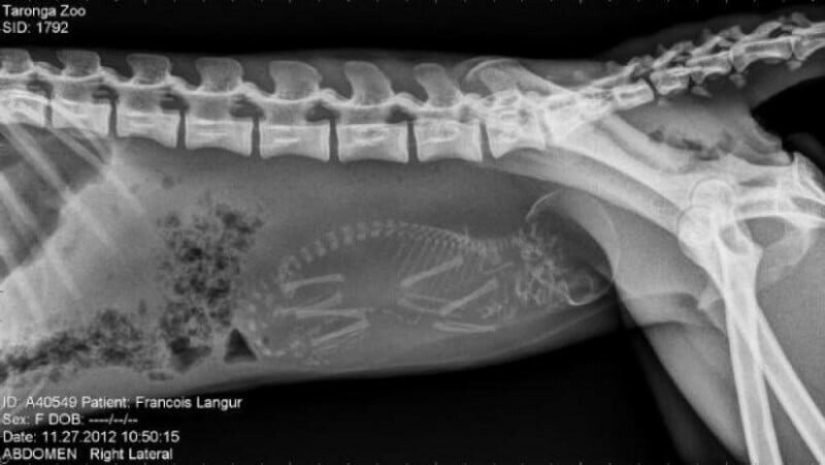

Quién vive en la casita: radiografías de animales preñados

Por Pictolic https://pictolic.com/es/article/quien-vive-en-la-casita-radiografas-de-animales-prenados.html¿Alguna vez te has preguntado qué sucede en el útero de una gata o una perra preñada? ¿Cómo encajan todos estos pequeños bebés allí y logran desarrollarse durante todo el embarazo? La mayoría de los animales preñados se examinan mediante rayos X. Y éstas, cabe señalar, son fotografías muy interesantes.

Especialistas que como parte de su trabajo observan animales que están listos para parir, compartieron estas sorprendentes imágenes de rayos X y ultrasonido.

mono preñado